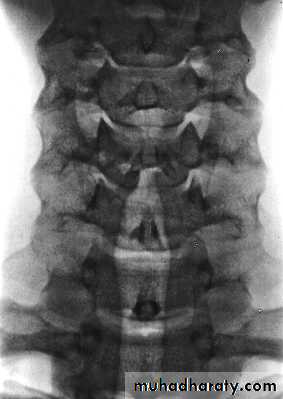

Cervical Spine X-RayLateral radiograph

A/P radiographThoracic Anatomy

Cervical Spine AnatomyNormal curvature is lordosis

Spinous Processes are BifidA flexible group of vertebrae that support the skull